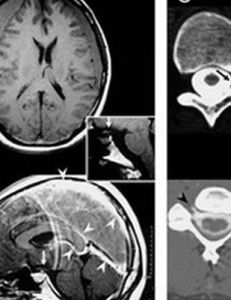

(3)腦血管造影、CT和磁共振等可間接診斷顱內高壓。